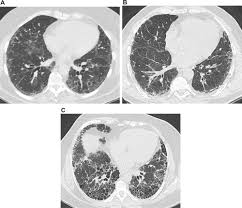

Asbestosis Pulmonary Disorders Msd Manual Professional Edition

Asbestosis Pulmonary Disorders Msd Manual Professional Edition from www.msdmanuals.com